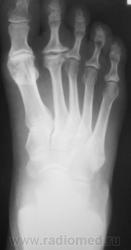

Травма. Пациент направлен на рентгенографию стопы.

основания 5 плюсны. ДОА плюснефаланговых суставов2-3 ст

перелом основания V плюсневой кости без смещения. остеохондропатия головок II-х плюсневых костей обеих стоп с формированием деформирующего остеоартроза. в области оснований II-III плюсневых левой стопы формирование по-типу неоартроза.

Перелом 5 плюсневой кости. Вторая болезнь Альбана Келера, 5 степень.